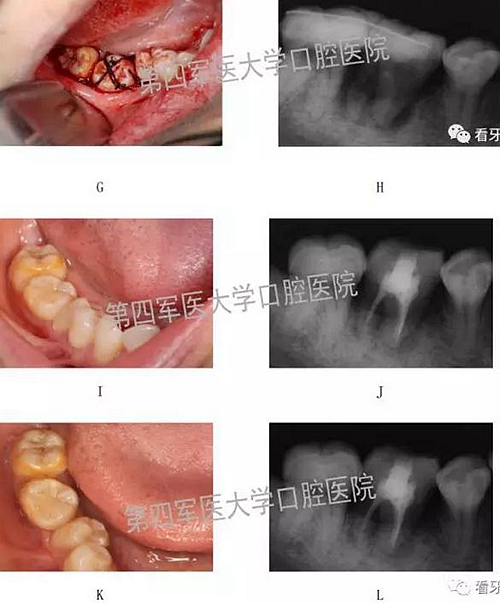

二,牙槽內移植

1,阻生牙牽出再值